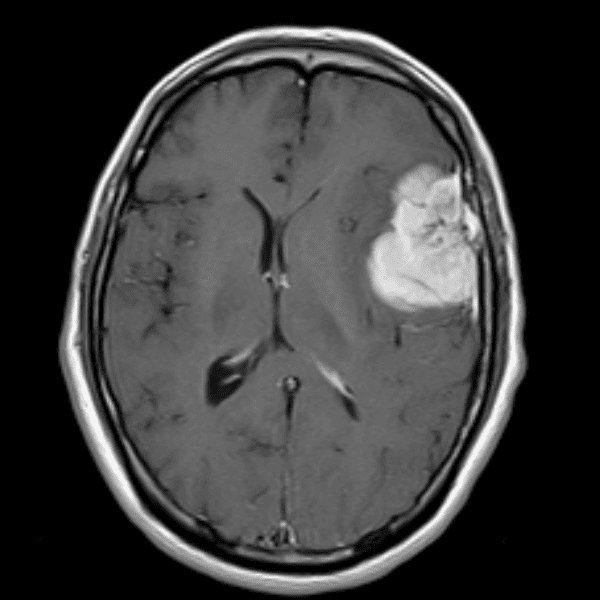

Classic Cases